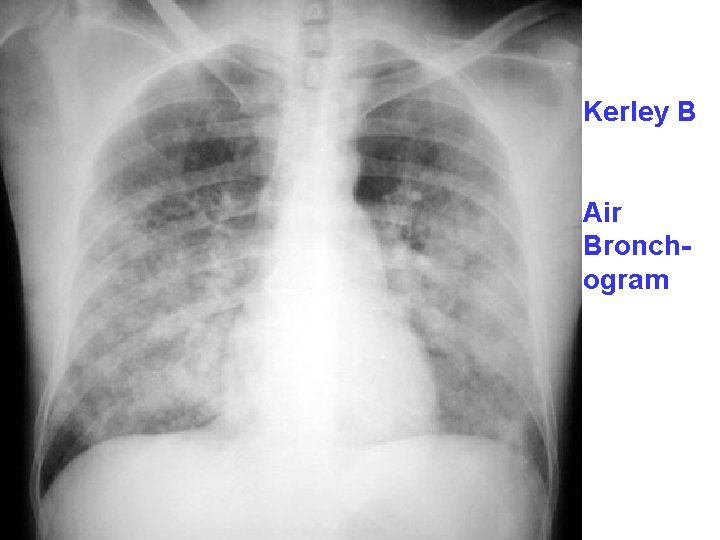

ACUTE PASSIVE HYPEREMIA/CONGESTION, LUNG

Kerley B Air Bronchogram

CHRONIC PASSIVE HYPEREMIA/CONGESTION, LUNG